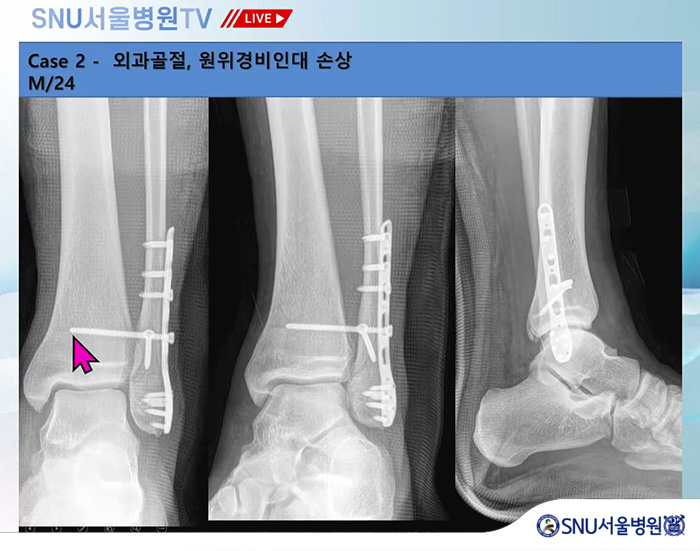

족부전담팀 강태병 원장님께서 직접 집도했던 여러 발목 골절 수술에 대한 사례를 직접 보여주며 설명해 주셨는데요!

발목 골절은 발이 어떻게 꺾이는 지에 따라 다양한 모양으로 골절된다고 하는데요.

골절이 어떻게 됐는지, 골절 모양에 따라 수술 진행 방법과 수술 후 재활이 조금씩 달라진다고 설명해주셨습니다.